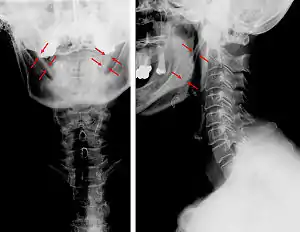

| Anteroposterior and lateral radiographs of cervical spine showing ossification of the stylohyoid ligament on both sides | |

Radiograph, lateral view showing elongated stylohyoid process and stylohyoid ligament ossification

CT scan, coronal section showing bilateral extended styloid process and stylohyoid ligament ossification (incidental finding)

Imaging is important and is diagnostic. Visualizing the styloid process on a CT scan with 3D reconstruction is the suggested imaging technique.[12] The enlarged styloid may be visible on an orthopantogram or a lateral soft tissue X ray of the neck.